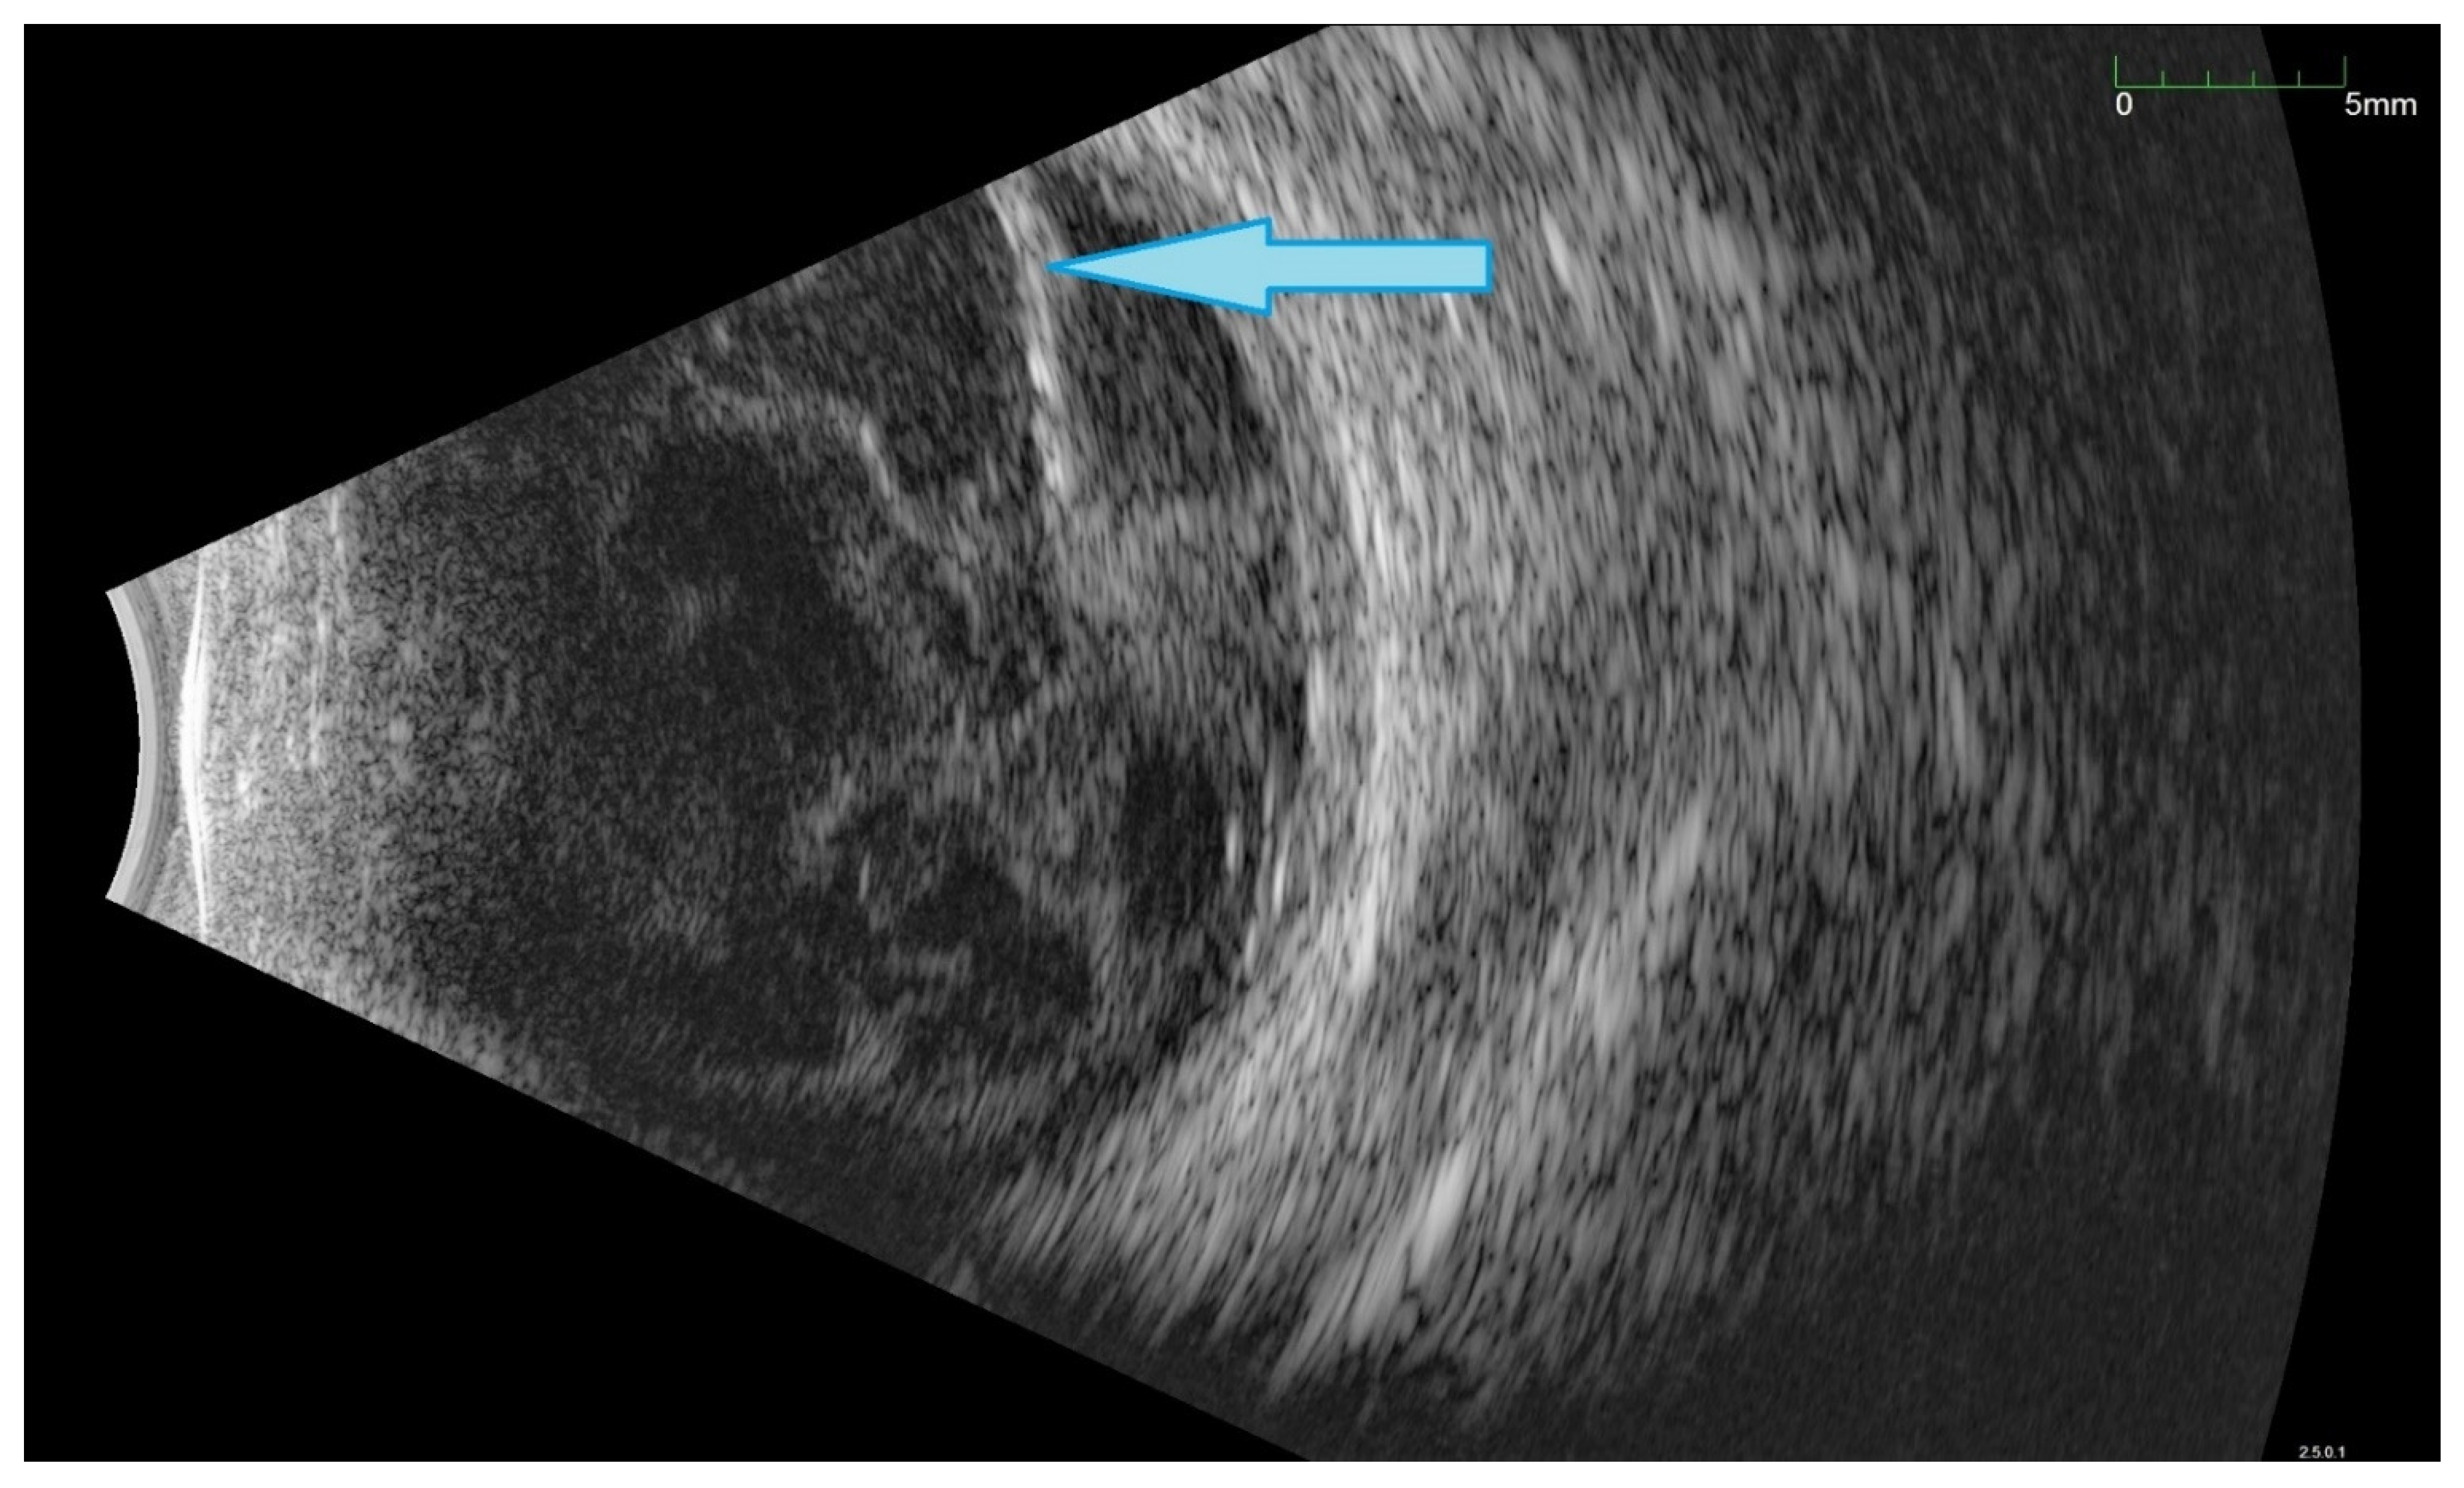

All of the above circumstances make the assessment of the vitreous body and retina in an ophthalmoscopic examination often impossible. The basic diagnostic tool in such cases is an ultrasound examination. Vitritis is inherent part of EE. Ultrasonography is nonspecific, however, it can indicate severity of the posterior involvement (Figure 6 and Figure 7) [80]. It also allows the assessment of the progression of changes (Figure 8). Features characteristic for EE include strands and membranes with reduced mobility (Figure 9). Other common changes are retinal detachment and subretinal abscess (Figure 10).

Figure 10.

Ultrasound B scan with numerous hyperechoic densities in vitreous chamber. The blue arrow marks a detached retina. Hyperechoic masses are visible under the retina.